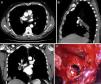

Chest computed tomography showing hypodense nodular images in the interior of the right pulmonary artery suggestive of cysts in the axial, sagittal, and coronal projections (A–C). Intra-operative view after clamping of the right pulmonary artery and arteriotomy of the lower lobe branch, showing hydatid membranes in the interior (D).

This was a 56-year-old man with no substance abuse or significant medical history who consulted his primary care physician due to a 2-week history of bloody expectoration accompanied by right chest pain. The chest radiograph revealed a polylobulated mass in the right lower lobe with hilar thickening, initially suggestive of lung cancer. Chest computed tomography showed a mass measuring 11×8.8cm in the right lower lobe with hypodense areas suggestive of cysts. The mass showed a 10cm contact with pleural surface, extending with peribronchovascular distribution toward the hilar region. Multiple nodular images of similar characteristics measuring up to 4.5cm were seen inside the artery. Radiological findings were suggestive of pulmonary hydatidosis with invasion of the right lower lobe artery (Fig. 1A–C).

Surgical resection was performed, and antiparasitic treatment continued throughout the peri-operative period. Intraoperative findings included hepatization of the lower right lobe, significant vascularization originating in the bronchial arteries, and increased caliber of the right lower lobe artery. After control and clamping of the right pulmonary artery at the extrapericardiac origin, arteriotomy was performed at the lower lobe branch, and the intravascular hydatid cysts were extracted (Fig. 1D). The proximal lumen of the pulmonary artery was aspirated to the level of the clamp. Given the significant perihilar inflammatory reaction, the proximal intermediate bronchus could not be resected, so a middle-lower bilobectomy was performed.